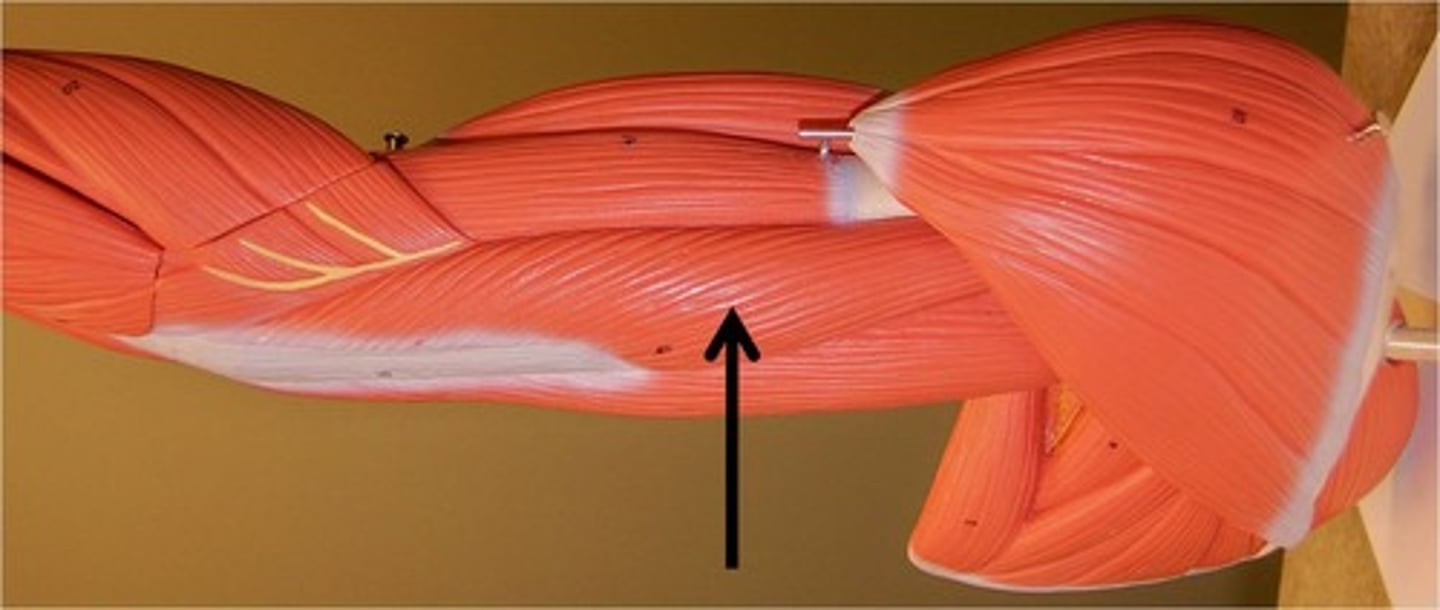

biceps femoris

extends thigh and flexes leg